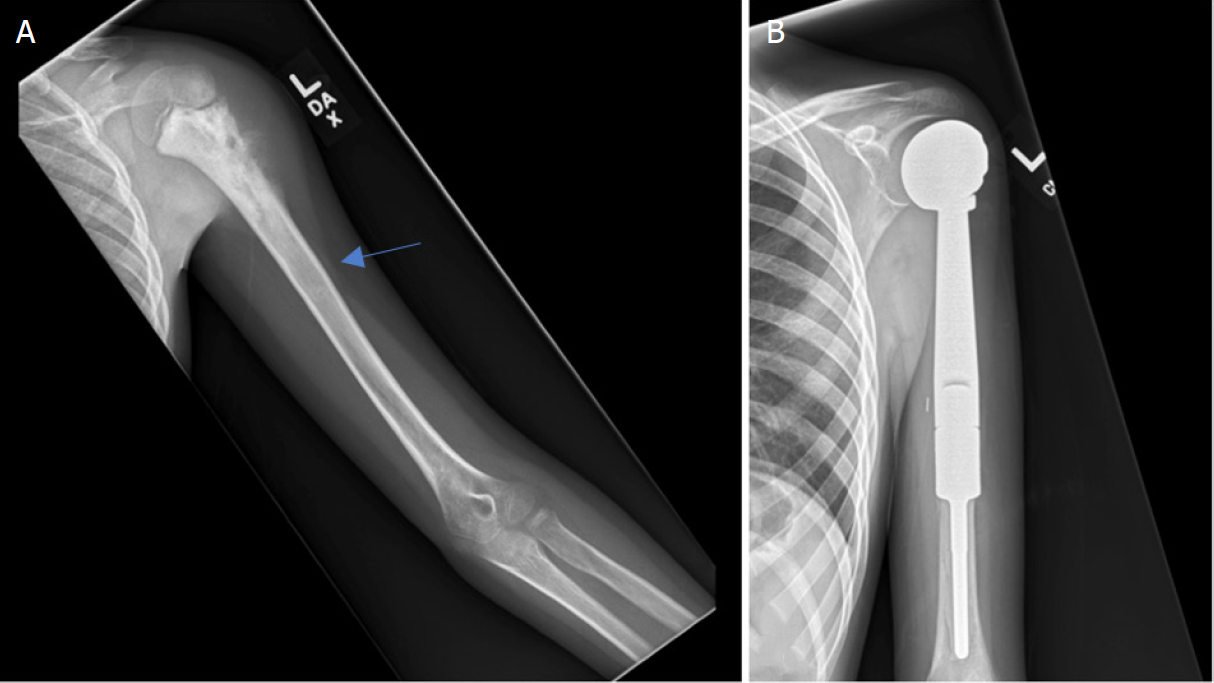

The Management of Metastatic Disease is Often Palliative

While primary bone cancers are the focus of curative treatment, the orthopedic oncologist also plays a critical role in managing patients whose cancer has spread from elsewhere in the body (e.g., breast, lung, prostate). The management of metastatic disease is often palliative, aimed at relieving pain, preventing imminent or pathological fractures, and maintaining the patient’s mobility and quality of life. Metastatic lesions frequently weaken the bone structure, creating a high risk of fracture from minimal trauma. The orthopedic intervention here is often prophylactic (preventative), involving stabilizing the threatened bone with rods, plates, or cement, or resecting the painful lesion. These procedures, while not curative, are profoundly important in allowing the patient to remain independent and comfortable during their systemic cancer treatment.